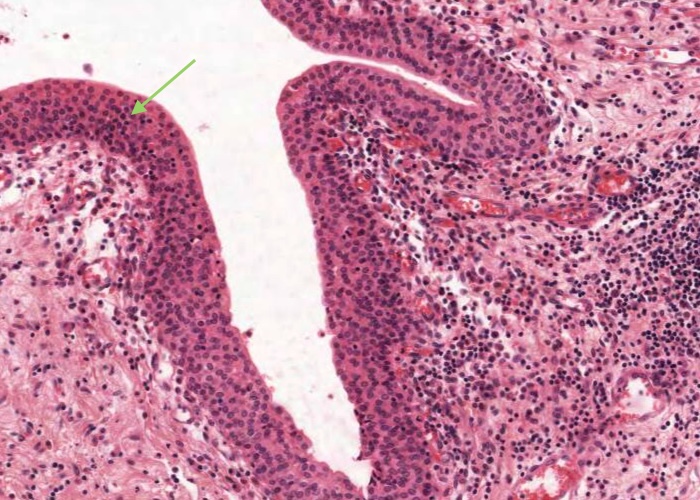

At low magnification, observe the three layers of the ureter: mucosa, muscularis and adventitia. This organization is maintained throughout the urinary passages. The mucosa of the ureter is thrown into characteristic longitudinal folds. It is made of transitional epithelium underlain by a layer of fairly cellular connective tissue (lamina propria). Quite a few lymphocytes are found in this lamina propria. The muscularis layer consists of two somewhat diffuse sheets of smooth muscle: the inner is longitudinal, and the outer is circular. Towards the bladder end it picks up a third oblique layer. This muscle produces peristaltic waves that push the urine to the bladder even when you are lying down. The adventitia is made of connective tissue and contains the nerves and blood vessels that supply the organ. One thing to note is that the ureter runs through loose connective tissue from the kidney to the bladder.

The ureter and also the other passages within the kidney through which urine flows i.e. the calyces and renal pelvis, are lined by transitional epithelium (often referred to as urothelium). The details of the layers of cells within this type of epithelium is best described in the later item "lumenal epithelium" of the bladder but generally it is 2-3 cell layers thick in the minor calyces but much thicker as you see here in the ureter and then the bladder.

Transitional epithelium is impermeable to water and salts and can accomodate the distension of the bladder as it fills with urine. In this image of "relaxed bladder" there are about 8 cell layers but make sure you notice how these layers "flatten out" in the "stretched bladder" image in the later item. Notice how the surface cells are cuboidal and bulge into the lumen of the bladder but their apex is curved or shaped like a dome so they are often referred to as "umbrella cells". The connective tissue below the epithelium is very cellular.